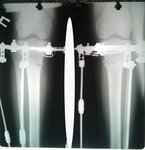

Рентген до операции.